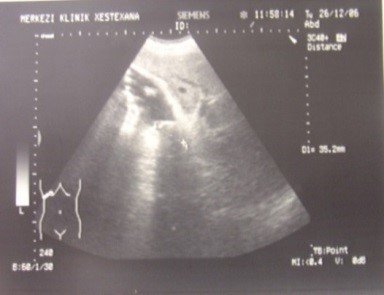

- Zədələnmələrin olub-olmamasını, yеrini və xaraktеrini dəqiqləşdirmək üçün xolangioqrafiya еdilir. MRT ilk seçimdir, lakin dəqiqləşdirmə üçün adətən kontrastlı xolangioqrafiya edilir: əməliyyat vaxtı əməliyyatdaxili xolangioqrafiya, əməliyyatdan sonra isə endoskopik və ya perkutan xolangioqrafiya.

- Öd yollarına yeridilən kontrastın kənara çıxması və ya “blok” (bağlanma) zədələnməni təsdiqləyən əlamətləridir.

Diaqnostik əlamətlər:

- Biliar sızıntı (peritonit, fistul, bilioma, qaraciyərdaxili abseslər) və / və ya mexaniki sarılıq

- Xolangioqrafiyada biliar ekstravazasiya və ya blok